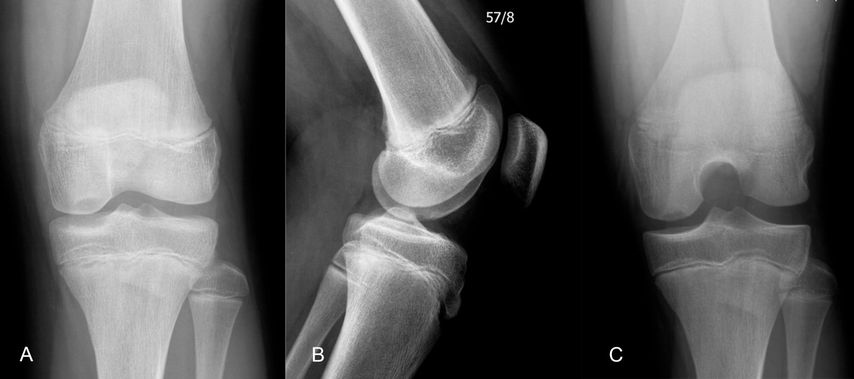

Abb. 4: 13-jähriger männlicher Patient mit einer instabilen Osteochondritis-dissecans-Läsion am posterolateralen medialen Femurkondyl präoperativ (A, D), 3 Monate (B, E) sowie 12 Monate (C, F) nach Refixation mittels Shark-Screw

Abb. 5:13-jähriger männlicher Patient mit einer instabilen Osteochondritis-dissecans-Läsion am posterolateralen medialen Femurkondyl präoperativ (A, C) sowie 12 Monate (B, D) nach Refixation mittels Shark-Screw